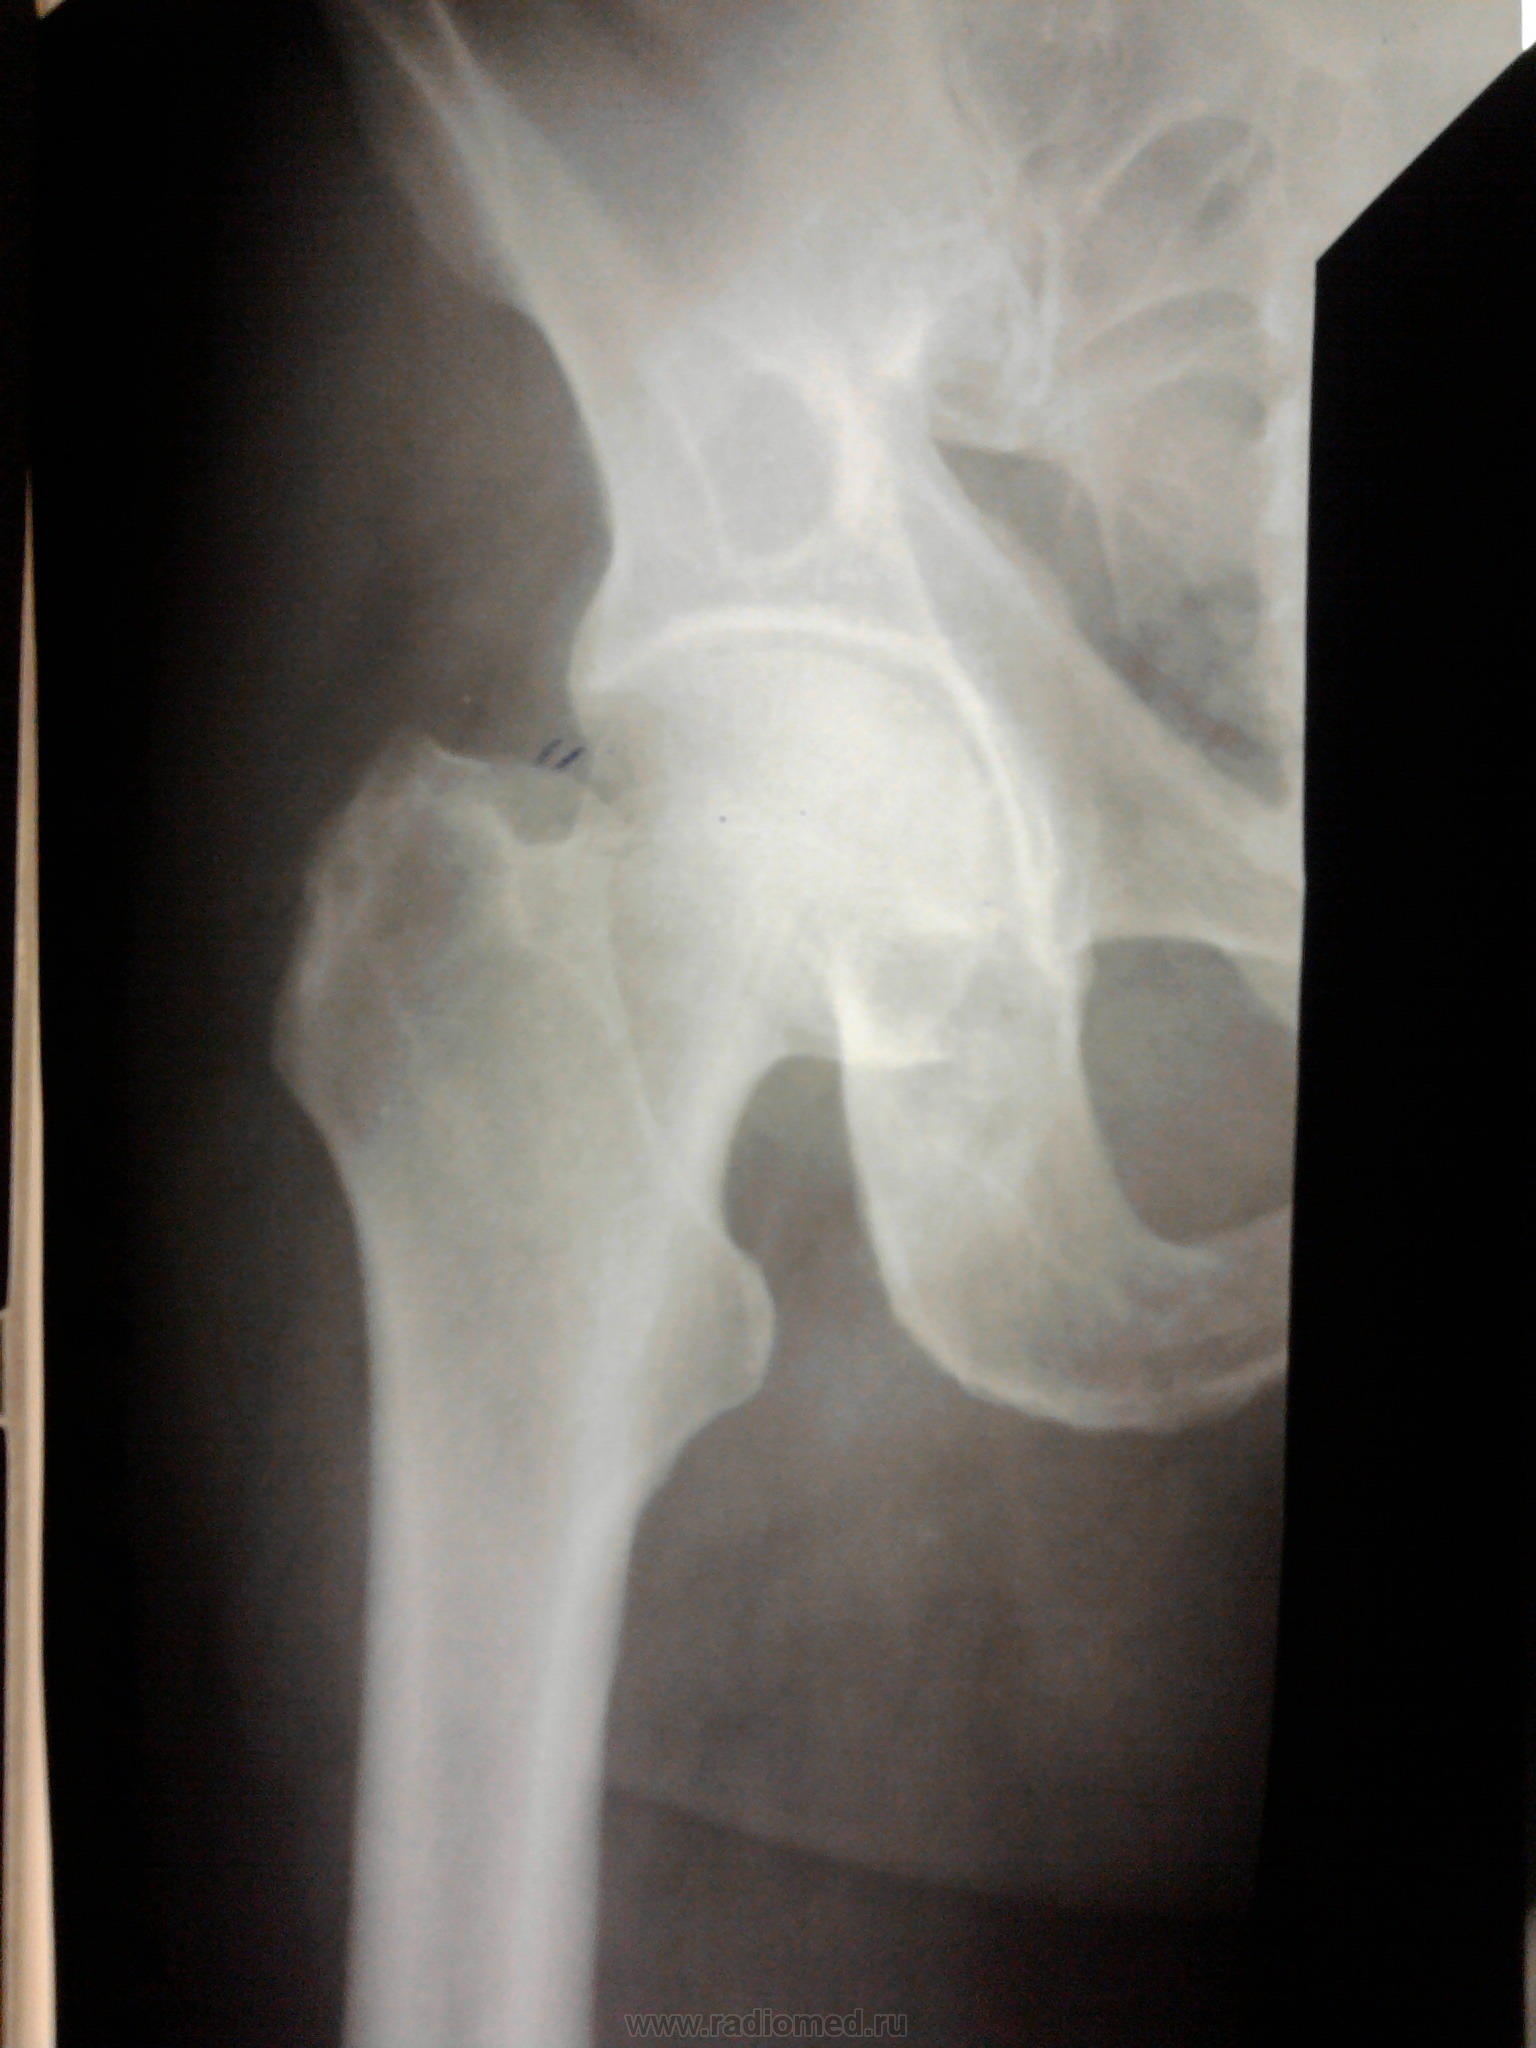

Двухсторонние литические очаги, с четкими, местами склерозироваными контурами. Старый консолидированый перелом левой бедренной кости, после металлоостеосинтеза металлической пластиной. Миеломная или мтс проявили бы себя более агрессивной деструкцией.

tatyana, Вам "зачет"! Здесь действительнро болезнь Реклингхаузена. Наблюдаю данного пациента лет 7. За это время его патологический перелом левой бедренной кости так и не срастается, приобретая все более атрофичный вид в виде перетяжки на уровне излома, потому и держат с металлом до сих пор. Классическая "пастушья палка". Справа в теле подвздошной кости и (менее выраженно) ближе к задней нижней ости, а также в большом вертеле также имеются литические очаги, относительно стабильные за время наблюдения.

"самоуверенность дилетантов - предмет зависти профессионалов"